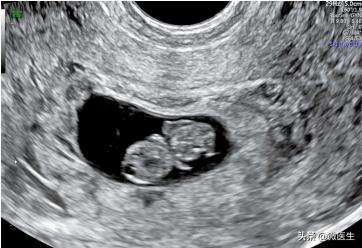

孕7周,经阴道超声检查显示卵黄囊(粗箭头)羊膜(长箭头)、胎芽(细箭头)、妊娠囊

孕8周,经腹部超声图像卵黄囊(粗箭头)、羊膜(长箭头)、胎芽(细箭头)